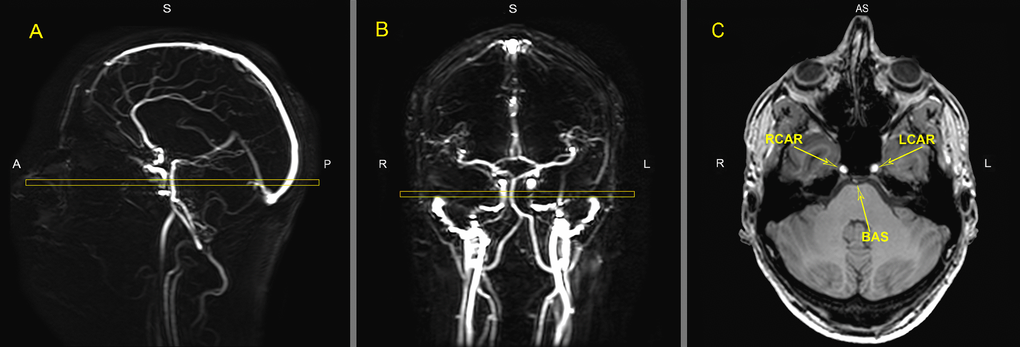

Phase contrast MR Angiography

Quantitative flow measurements were performed using ungated phase-contrast MRA, based on 2 localizer MR angiograms in the sagittal and coronal orientation as shown in Figure 5. A region of interest (ROI) was drawn around the vessel lumen on the magnitude images by an experienced rater using Philips Software on a PACS (Philips Medical Systems, Best, The Netherlands) workstation with ROI measurement tools. Flux was measured for basilar artery and both internal carotid arteries separately. Total flux was calculated for all three vessels together.

Figure 5. MR images of the vasculature measured with phase contrast MR angiography imaging for Quantitative Flow (QF). Typical placement of the QF phase-contrast slice (C) through the right internal carotid artery (RCAR), left internal carotid artery (LCAR) and the basilar artery (BAS) using the sagittal (A) and coronal (B) localizer angiograms. ROI’s were drawn around the three arteries in slice C to measure flow.